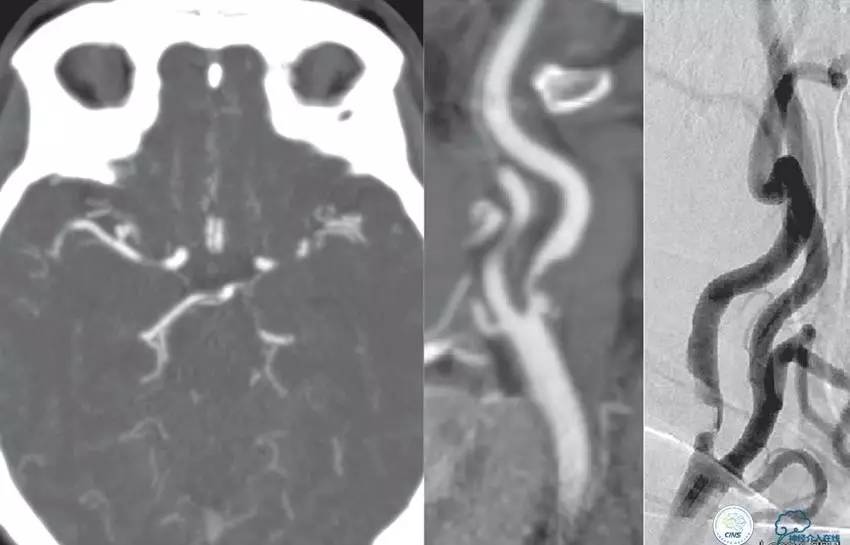

患者:徐XX,男,38岁,既往高血压病史1年。

现病史:患者2012年11月26日,2:00PM左右无明显原因出现头晕,不伴头痛,无视物成双,症状持续存在,无明显好转,遂到当地医院就诊,颅脑CT未见出血。5:50PM出现左侧肢体活动失灵,手脚不能活动,伴有左侧口角歪斜,无肢体抽搐及意识障碍,言语尚可。9:00PM左右到我院急诊室,述途中肢体一度恢复活动。

查体:两侧瞳孔等大等圆,对光反射灵敏。左侧肢体肌力2级。NIHSS评分8分,急诊查心电图、血常规、肝肾功、凝血四项、心肌酶等未见明显异常。急诊颅脑CT未见出血。

▼L-CCA

检查右侧肢体肌力,未见明显异常。

尿激酶20万单位,动脉导管内推注。

口服拜阿司匹林300mg,再次取栓。

2.0×15mm球囊扩张V4段狭窄。

Penumbra 导管再次取栓。

▼R-VA

▼第三天MRA